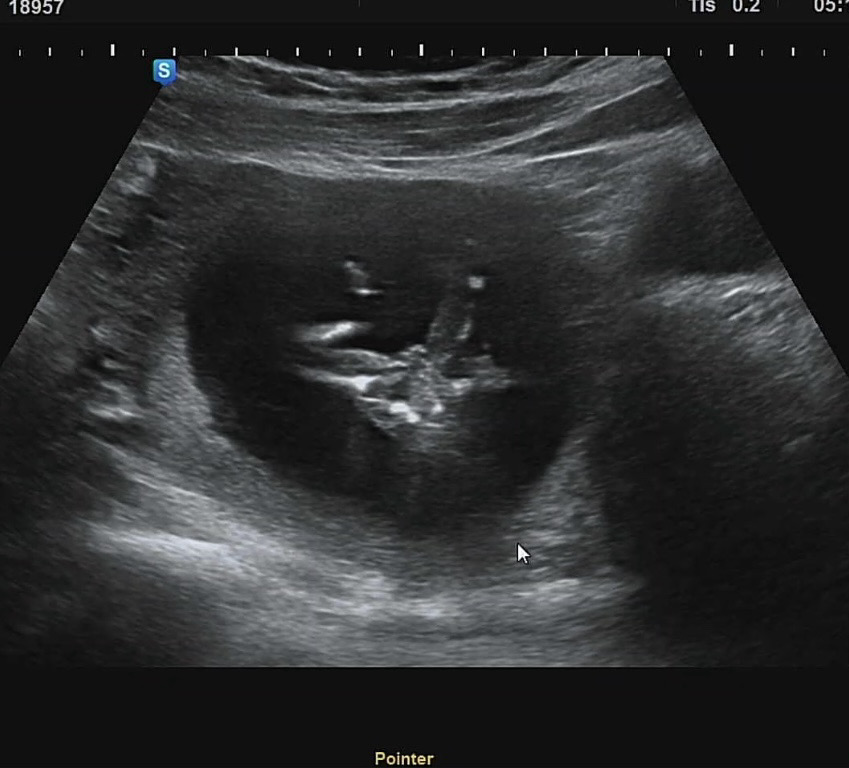

13주5일 초음파 (딸소견)

오늘 서브 병원가서 초음파 보고 왔어요~ 쌤이 다리사이가 매끈하다구 딸일 확률이 높다고 반전될 확률이 적다고 하시더라구여! 여기 계신분들도 100퍼 딸 같나용~~?

100퍼라고 하기엔 완전 매끈한 느낌은 아니네용 ㅎㅎ그래도 의사샘이 딸소견 주셨으니까 맞겠죵 !